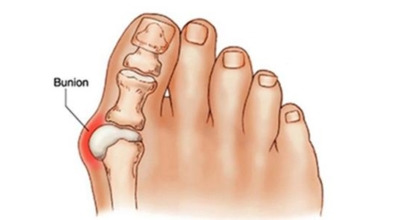

무지외반증은 엄지발가락이 두 번째 발가락 쪽으로 과도하게 휘고, 그와 함께 엄지발가락과 연결된 중족골이 안쪽으로 치우쳐 변형되는 상태입니다. 또한, 발가락이 발등 쪽으로 휘거나 회전하는 삼차원적인 변형을 일으킬 수 있습니다.

무지외반증이 진행되면 육안으로 엄지발가락의 변형이 뚜렷하게 나타납니다. 초기에는 굳은살이 생기고 약간의 통증이 동반될 수 있습니다. 엄지발가락이 돌출된 부위는 신발에 자극을 받아 두꺼워지고 염증이 발생하여 통증이 생깁니다. 발바닥이 휘어지지 않더라도 굳은살 때문에 정상적인 보행이 어려워지고, 심한 경우에는 통증으로 인해 신발을 신는 것조차 힘들어질 수 있습니다. 증상이 계속 악화되면 엄지발가락이 겹쳐지거나 탈구되는 경우도 발생할 수 있습니다.

또한, 엄지발가락이 옆으로 휘어지면서 관절에 비정상적인 압력이 가해져 퇴행성 관절염이 생길 수 있습니다. 엄지발가락이 발바닥의 압력을 지지하지 못하게 되면, 2, 3번째 발가락으로 그 부담이 옮겨져 발바닥에 굳은살이 생기고, 발가락 뼈 사이의 신경이 부풀어 통증을 일으키는 지간신경종이 발생할 수 있습니다.